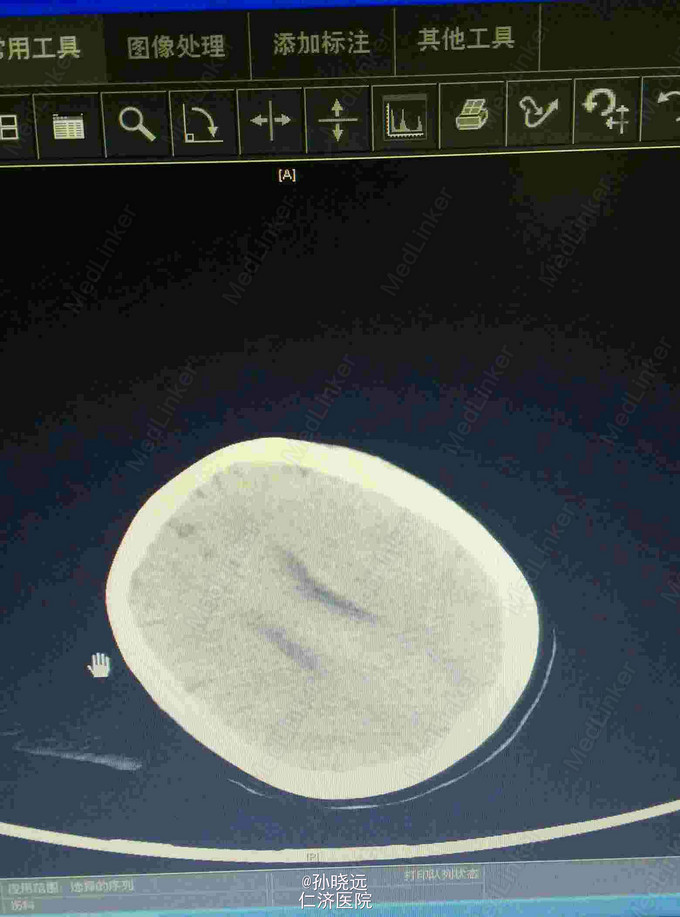

中年女性。主诉:头晕三天,发热伴神志不清1天。 患者于三天前出现持续性头晕,无恶心、呕吐,无视物旋转,来院就诊,查头颅MRI未见异常,予桂哌齐特、长春西汀、硫辛酸治疗,症状无好转。1天前出现高热,最高39.5℃,无咳嗽、气促,再次来院就诊,查血常规:WBC:5.85*10^9/L,N:71.8%,CRP正常,予退热,阿奇霉素等治疗,今日凌晨出现神志不清,无抽搐、恶心、呕吐,头颅CT示两侧颞底部不规则斑点样密度增高影并周围低密度灶,考虑脑炎合并灶性出血,予更昔洛韦、醒脑静、喜炎平、奥美拉唑、甘露醇治疗。后出现氧饱和度下降,予气管插管有创呼吸机辅助通气。 既往史:曾有高血压病史,未应用降压药。

诊断:脑炎。脑出血。 治疗:甲强龙抗炎,更昔洛韦,青霉素钠抗感染,降压,甘露醇、甘油果糖、白蛋白、拖拉塞米里降颅压,呼吸机辅助通气等对症治疗。

腰穿是: 脑脊液生化:葡萄糖:12.18mmol/L,CL:110.9mmol/L,蛋白:222.4mg/dl, 脑脊液常规:淡黄,微混。红细胞:1000*10^6/L,白细胞:1059*10^6/L,潘氏试验阳性(++++),嗜中性粒细胞12%,淋巴细胞:80%,单核细胞8%,凝块无,细菌未找到。 予加用血必净,加强抗感染等治疗。 患者目前仍昏迷,正进行高压氧仓治疗。这是最近一次复查的头颅CT。